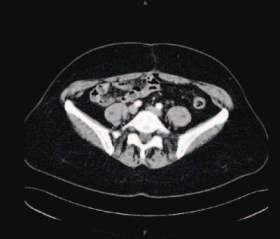

Obrázky 1 a 3 ukazují nález octreoscanu před operací a po radikální operaci, obrázky 2 a 4 ukazují totéž na CT. Obrázek 5 demonstruje echokar biografický nález významné trikuspidální regurgitace, obrázek 6 ukazuje normalizaci onkomarkerů sérového chromograninu A a obrázek 7 normalizaci hodnot odpadů 5 - hydroxyindoloctové kyseliny (5 - HIOK) v moči. Hodnoty CA 125 byly v celém průběhu v normě.

CT po radikálním odstranění karcinoidu ovaria